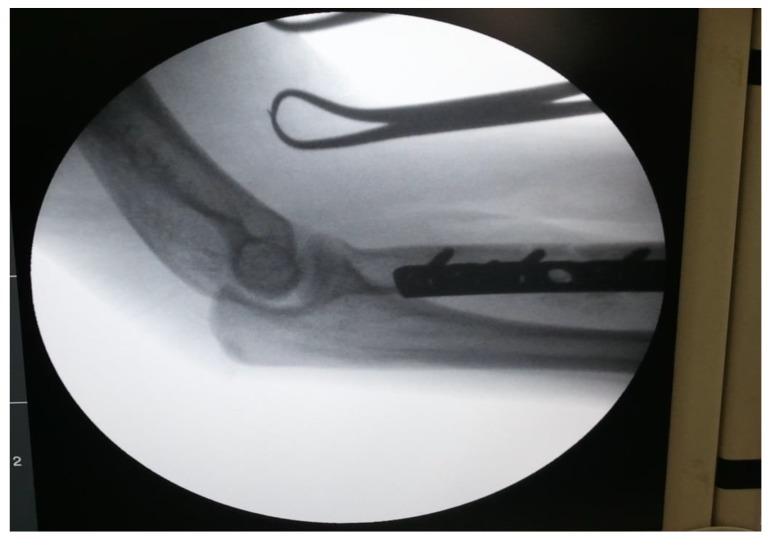

CASE PRESENTATION

We are reporting a case of a young adult male who was operated for proximal one-third radial shaft fracture at some peripheral centre by Open Reduction and Internal Fixation (ORIF), but came to our centre on the fourth post-operative day with complaints of painful restricted movements of the elbow joint. On careful look at the postoperative x-ray, radial head was found to be dislocated. Radial head dislocation was reduced under general anesthesia and at 2 years follow up, patient fracture has fully united having good functional outcome.

我们报告一例年轻成年男性病例,该患者在某外周中心因桡骨近端三分之一骨折接受切开复位内固定术(ORIF),但术后第四天因肘关节疼痛性活动受限前来我院。仔细查看术后X线片发现桡骨头脱位。在全身麻醉下对桡骨头脱位进行了复位,随访2年时,患者骨折已完全愈合,功能恢复良好。